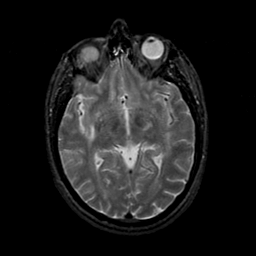

MR Study #23, January 26, 1992 -- Slice #23